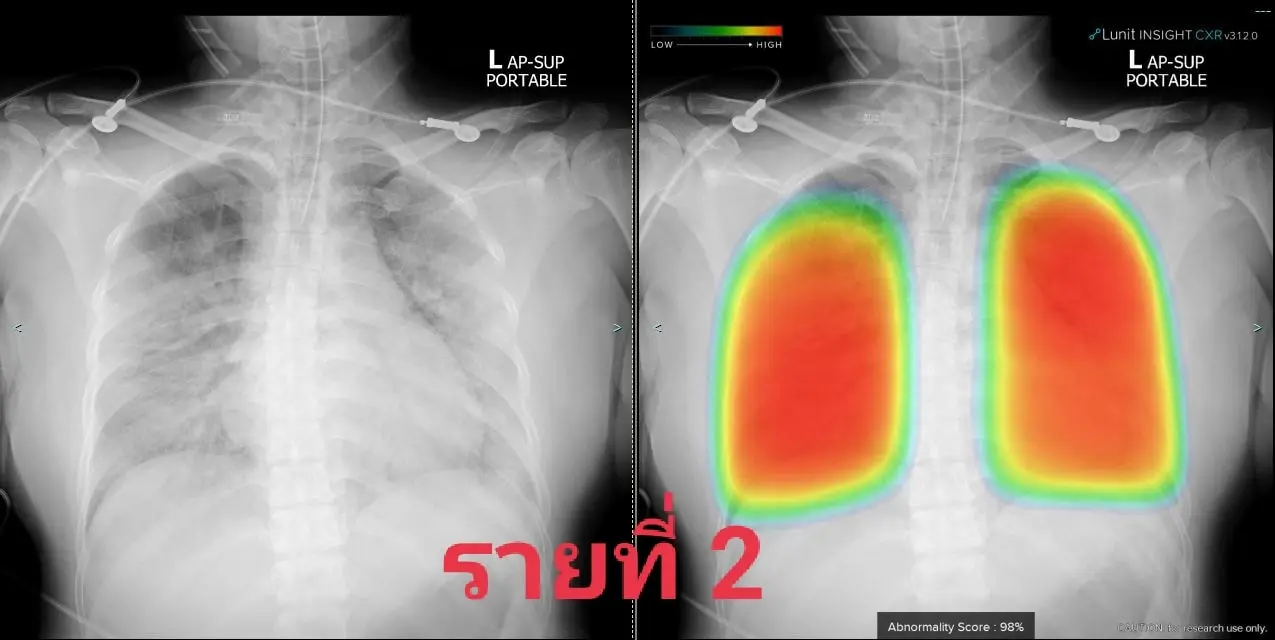

2. หญิง 39 ปีเดิมแข็งแรงดี

ทั้งสามคนอยู่ในพื้นที่ท่าพระ-ภาษีเจริญ โดยติดเชื้อกันส่วนใหญ่หรือทั้งครอบครัว พวกเขามารพ.ศิริราชด้วยอาการของปอดอักเสบโควิดรุนแรง รายแรกต้องใส่ท่อช่วยหายใจขณะนำส่ง รายที่สองใส่ทันทีเมื่อถึงรพ. ส่วนรายที่สามใช้ไฮโฟลว์ได้พักหนึ่งแล้วไม่ไหวต้องใส่ท่อ

ทั้งสามคนต้องรอเตียงย้ายเข้าไอซียูโควิดกันไม่น้อยกว่า 12 ชม. โชคดีว่าทีมเราเอาท่อช่วยหายใจผู้ป่วยออกได้สี่คนในช่วงสองวันนี้และย้ายออกไปได้สามคน จึงทยอยรับทั้งหมดเข้ามาไอซียูโควิดที่ทีมเราดูแลได้ แต่หากมีรายแบบนี้มาอีกคงหาจังหวะเหมาะเจาะเช่นนี้ไม่ได้อีกแล้วลองดูเอกซเรย์ปอดกันหน่อย พบมีฝ้าขาวเวอร์กระจายทั่วปอดในทุกคน จนเจ้า AI ที่ช่วยงานเรายังให้สีแดงแจ๋บ่งถึงรุนแรงน่ากลัวมาก